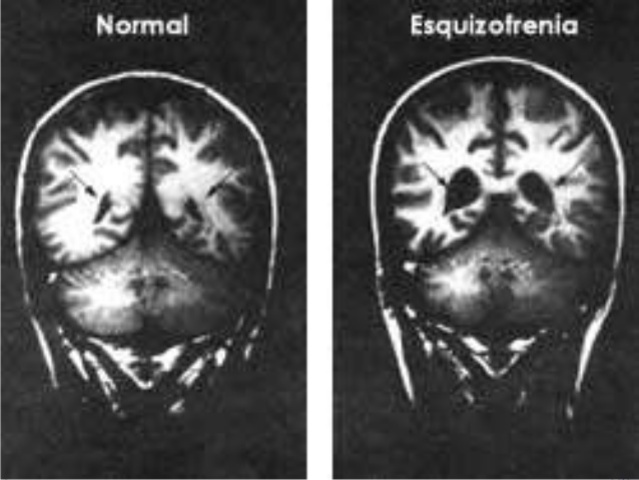

--> WHAT IS PARANOID SCHIZOPHRENIA?

Is a mental illness that does not entail observable anatomical alteration, and whose main characteristic is that it affects the personality of the individual, as well as to areas of his psychology. This disorder is often linked to others in the affectivity and thought.

Paranoid: It is the most common. Its symptoms are delusions (false, true, or indeterminate perceptions or beliefs) and frequent auditory hallucinations.